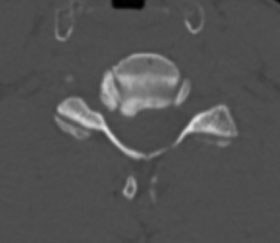

Під час огляду було виявлено значне звуження корінцевого каналу С6 корінця, яке викликало подібну симптоматику. Такі звуження корінцевих каналів виникають, як правило, при випинанні кили диску або при розростанні кісткової тканини тіл хребців та суглобових відростків. Це приводить до затискання корінця. Такий стан вилікувати консервативно практично неможливо.

Операцію в цьому випадку повинна включати видалення зайвих кісткових та м’якотканинних структур (диски, зв’язки) для декомпресії корінця та стабілізацію хребта. Але є альтернативні види втручань, коли видалення кісткових та зв’язкових структур не обов’язково вимагає фіксації. До таких процедур відноситься передня декомпресія корінця. Під час процедури видаляється мінімальна кількість кісткової та сполучної тканини, що дозволяє сегменту (2 суміжних тіла хребця та диск) залишитися стабільним.